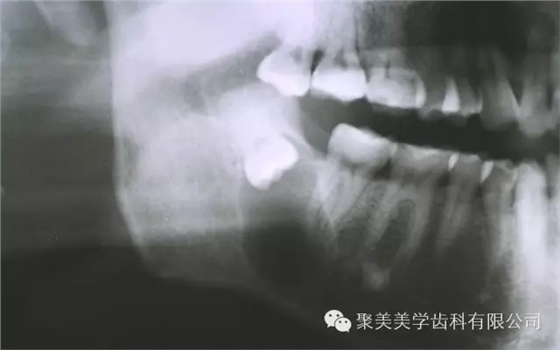

阻生牙不拔,形成囊腫!